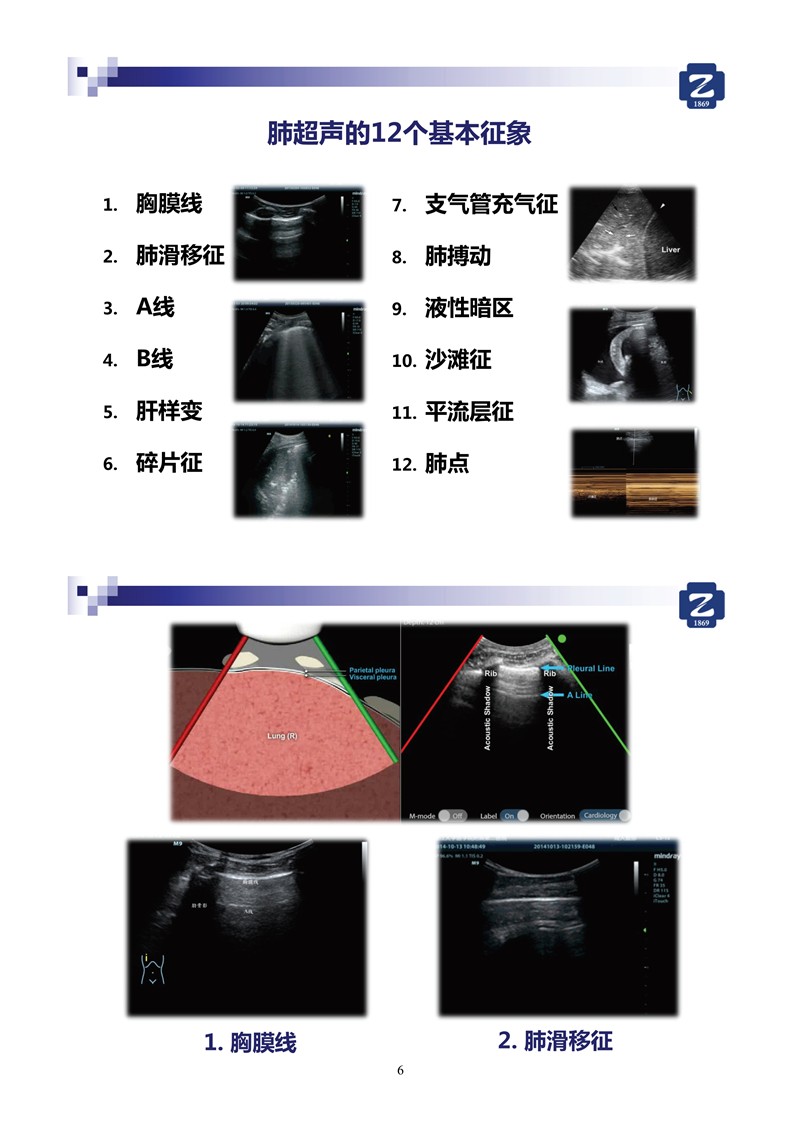

第一版新型冠狀病毒肺炎超聲診斷實(shí)用手冊(全文)